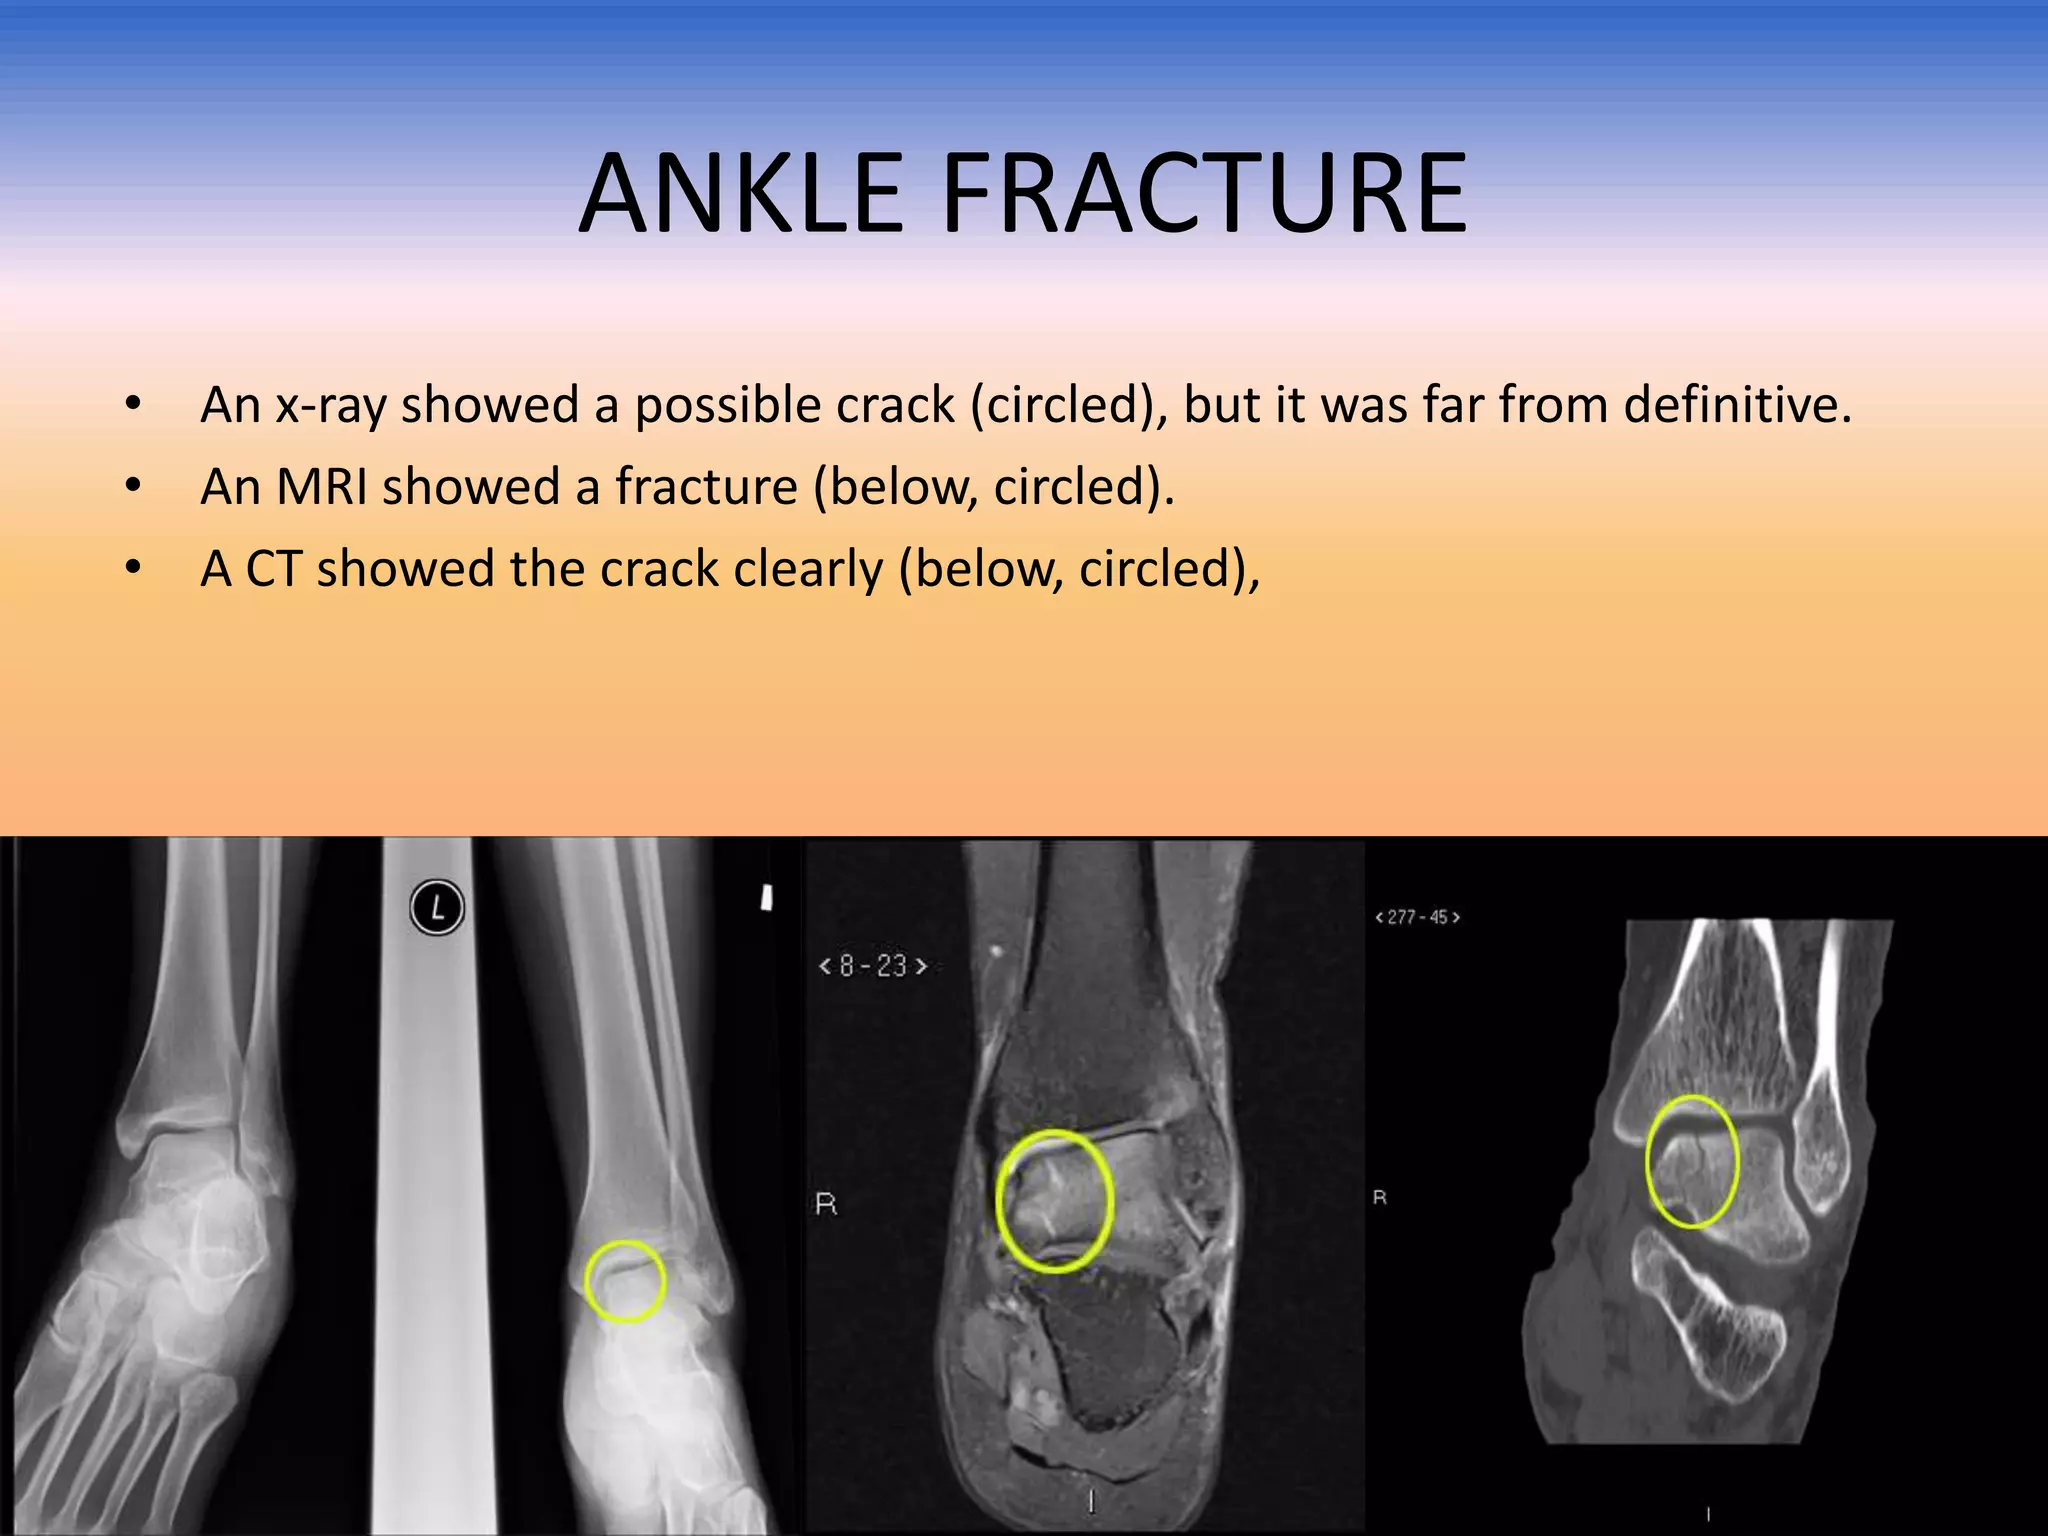

ANKLE FRACTURE

• An x-ray showed a possible crack (circled), but it was far from definitive.

• An MRI showed a fracture (below, circled).

• A CT showed the crack clearly (below, circled),